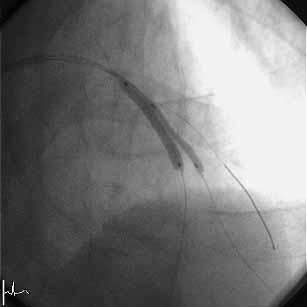

�͂��߂܂��āB���A�r58�N���̒��N��t�ł��B���͂܂��sRA�ł̃C���^�[�x���V����

�͖��o���ł��B�����~���L�b�g���łĂ���A�܂����ꂽfemoral�ł�������TFA�𑱂�

�Ă��܂������A��͂芳�҂���̖����x��radial���ォ�ȂƊ�����悤�ɂȂ�ATRA

��try���悤���Ǝv���͂��߂Ă��Ă��܂��B���낢��������Ē��������Ǝv���܂�

�̂ŁA��낵�����肢�������܂��B

�F����ɂ��ӌ��������Ǘ�̂o�b�h���s���܂����B

�VFr.TFI�A�K�C�h�J�e�W���h�L���X4.0�V���[�g�`�b�v

�P�ALAD�݂̂Ƀ��C���[�N���X���AIVUS�Ŋώ@�B

�Q�A�J���^���}�[�x���b�N4.5-8mm�ɂ�LMT�����v�����ADriver 4.0-9mm��I���B

�i�O�g���͂��Ă��Ȃ��j

�R�A�X�e���g���P�Q�C���Ŋg����AIVUS�B

�S�A�J���^���}�[�x���b�N4.5-8mm�Ō�g�����s���AIVUS�B

�T�A����ɃJ���^���}�[�x���b�N5.0-8mm�Ŋg����AIVUS���A�I���B